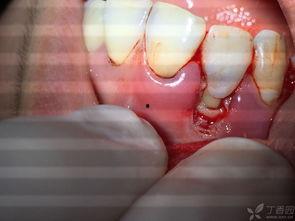

来看看这些牙龈烂了的图片,是不是觉得有点吓人?红肿的牙龈,甚至可以看到一些小洞洞,这就是牙龈炎的典型表现。如果你发现自己也有类似的情况,那可要赶紧重视起来了!